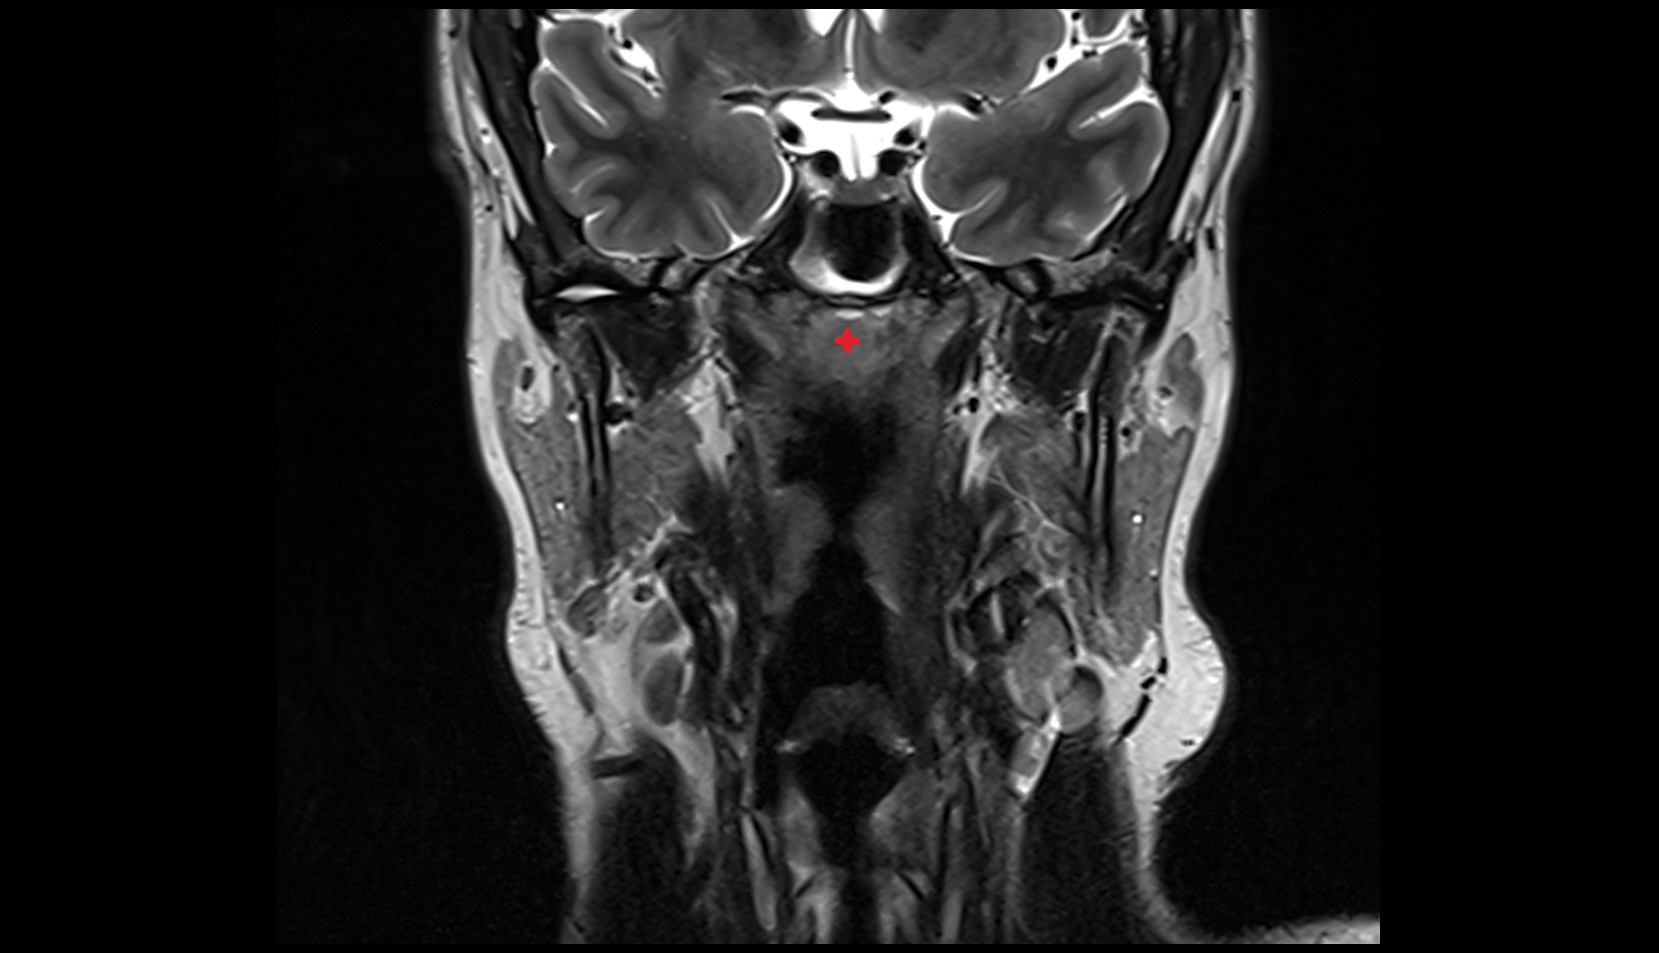

- Meckel’s cave (Trigeminal cave)

- Trigeminal cave

- Trigeminal ganglion

- Trigeminal nerve (Cranial nerve V)